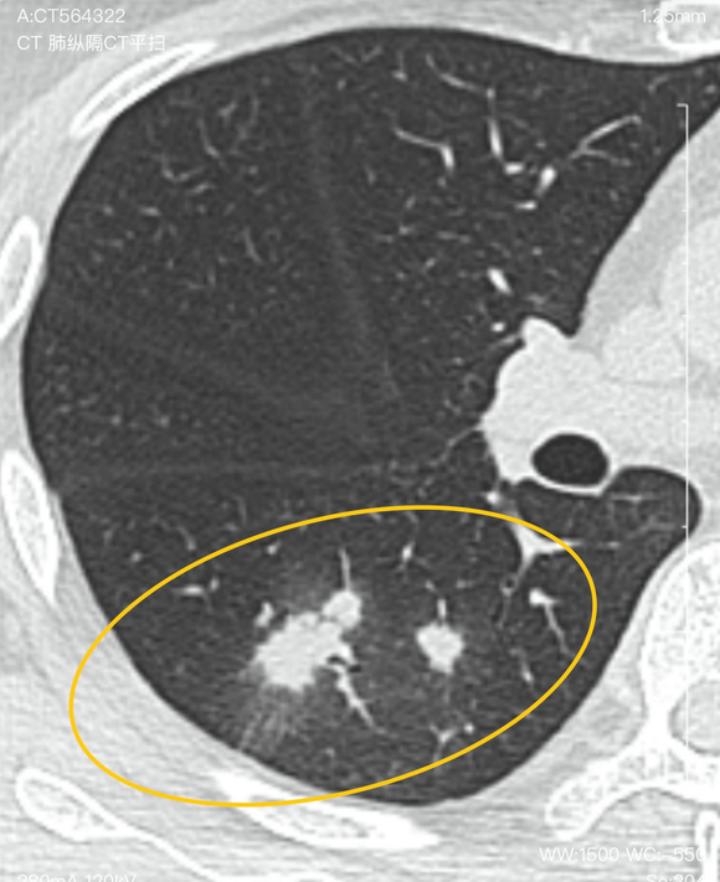

但是右肺下叶新发一个8mm的结节,还有多发斑片状磨玻璃密度灶。主任当时留言说考虑炎性,应该能消。吃莫西沙星12天又过了半个月复查,发现结节增大到2.4cm。医生说得住院检查。还建议穿刺!

看完片子,在这种情况下,可以断定是感染性病变。因为他结节的尺寸变化就符合感染性病变的特性。在抗炎处理的情况下,结节的尺寸从8mm增大到了24mm,体积翻了近20倍,直接排除肺癌和其他结节所致。那么首先考虑的是结核,其次考虑的是真菌感染(这可能也是抗炎处理无果的原因)。不过不用着急,现在肯定是良性的病变,后期可控,勿忧。

感染性病变,首先考虑结核,真菌感染不除外。